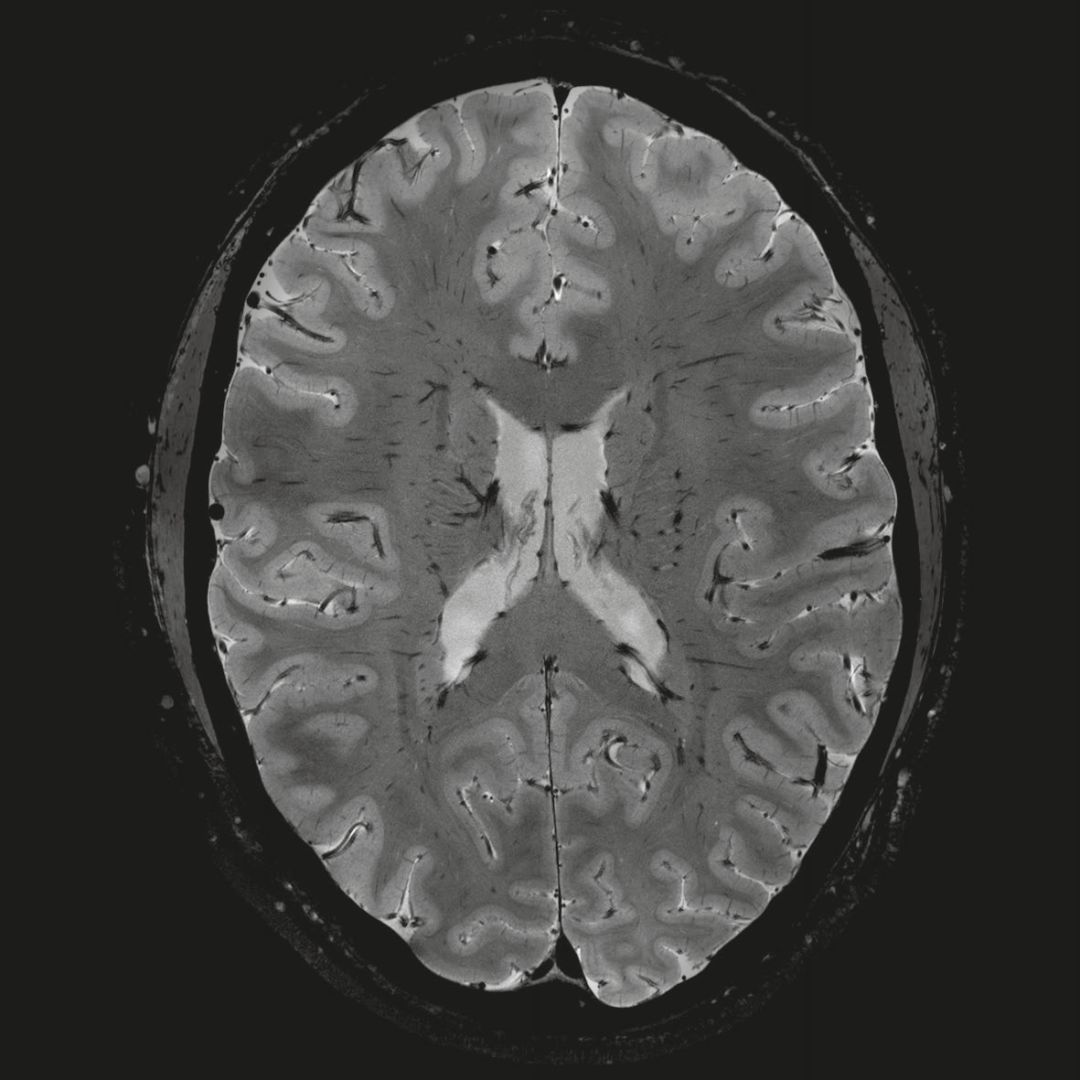

但近年來(lái),西門(mén)子與科研機(jī)構(gòu)共同研究發(fā)現(xiàn),7T提供了數(shù)倍于傳統(tǒng)3T磁共振的信噪比和空間分辨率,在神經(jīng)、血管、腫瘤、骨關(guān)節(jié)等多個(gè)方面都會(huì)帶來(lái)全新的突破性進(jìn)展。尤其是在目前常規(guī)影像設(shè)備難以診斷的神經(jīng)退行性疾病如阿茲海默氏病、帕金森病等疾病的發(fā)病機(jī)理、早期診斷、治療方案確定以及治療效果評(píng)估上,有著極大的潛力。

• 第三,.業(yè)界最高的射頻系統(tǒng)

MAGNETOM Terra使用Tim 技術(shù),可以獲得超高通道數(shù)的獨(dú)立射頻數(shù)據(jù)接收能力,為臨床提供了更為強(qiáng)大的系統(tǒng)采集能力,數(shù)據(jù)采集能力達(dá)到傳統(tǒng)7T兩倍,帶來(lái)無(wú)窮的科研可能。

超精細(xì)的解剖細(xì)節(jié):T2對(duì)比

0.17 x 0.17 x 0.8毫米分辨率超高。

(TOF)300微米的各向同性分辨率顯示最小的血管